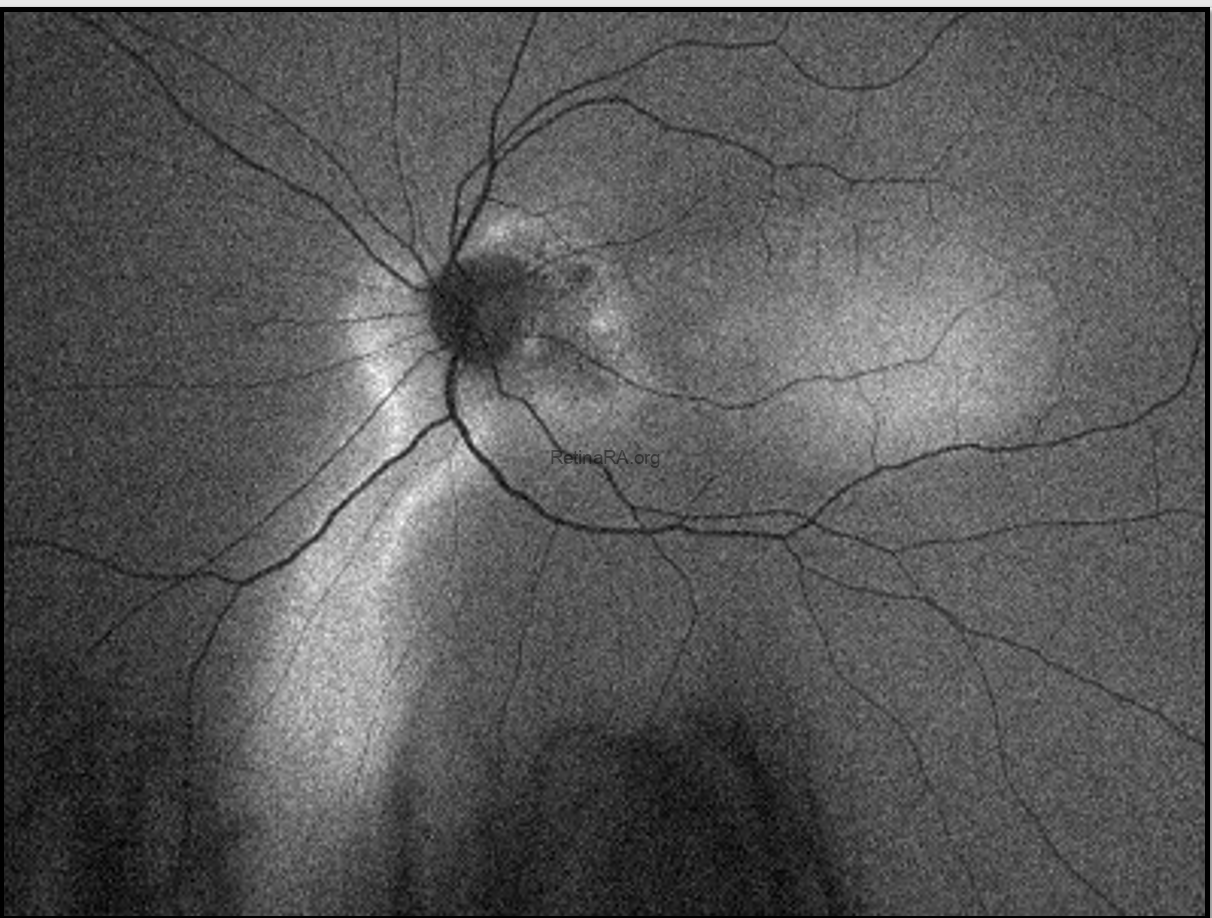

Ultra-widefield autofluorescence revealed hypoautofluorescent gravitational tracks corresponding to areas of RPE atrophy, surrounded by hyperautofluorescent borders indicating ongoing RPE dysfunction.